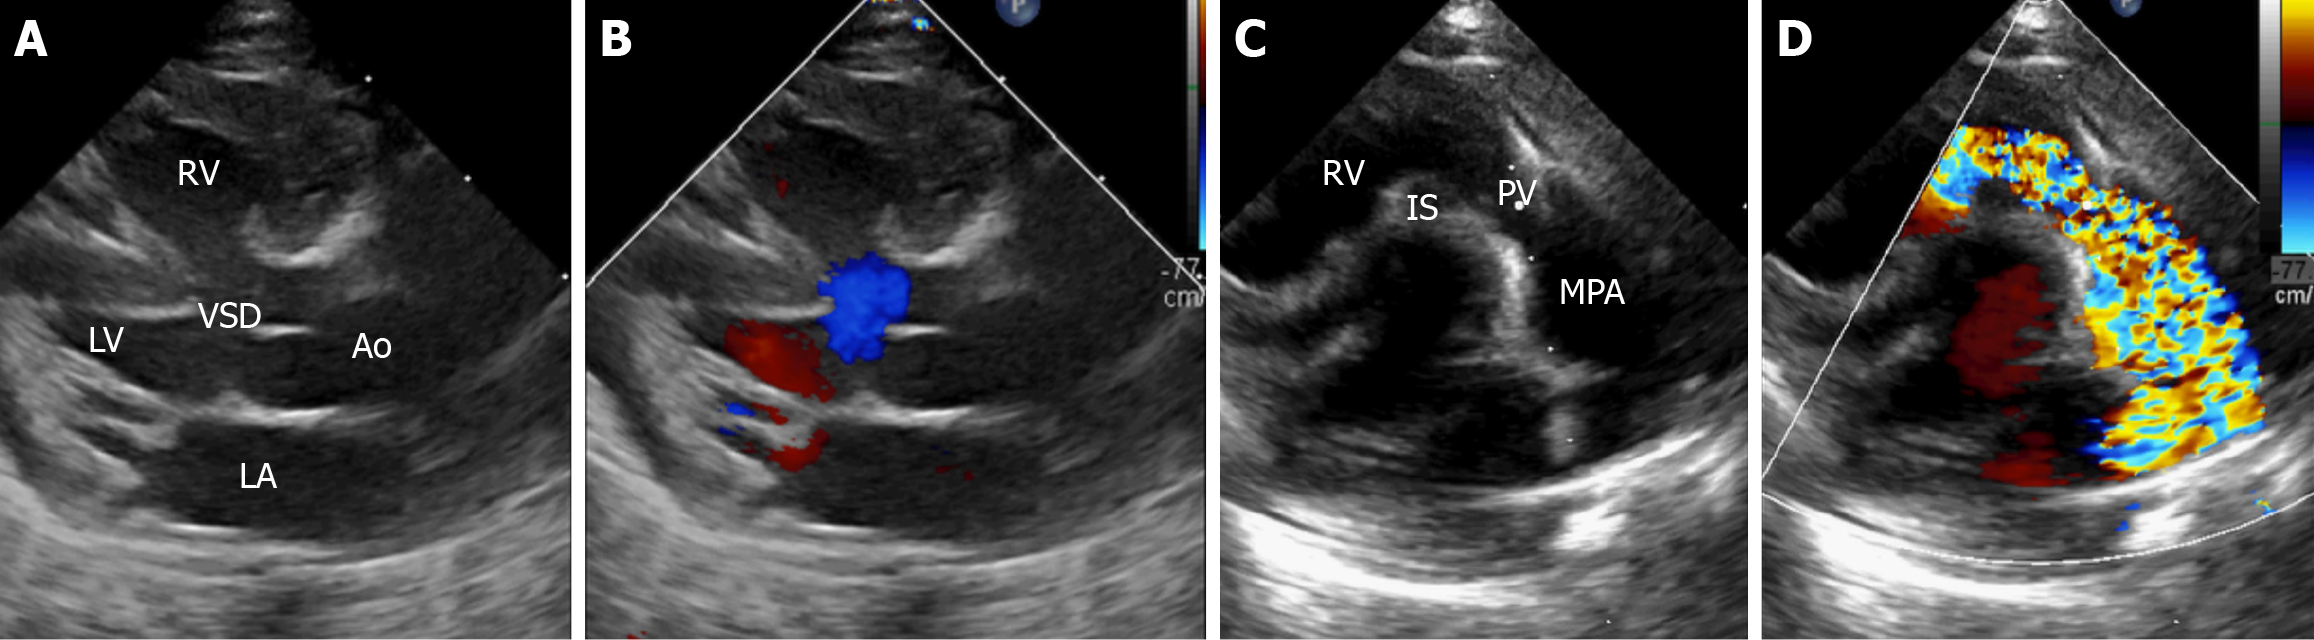

TTE

TTE is the principal and initial investigation of choice in patients less than 10 years of age, where the acoustic window is usually good. The parameters assessed on pre-operative TTE are outlined in Table 1 and depicted in Figure 2[16-18]. Detailed insights into right ventricle mechanics can be provided by using strain imaging, tissue Doppler, and speckle tracking with three-dimensional echocardiography, improving spatial resolution. Postoperative echocardiography in TOF includes assessment of the surgical repair, any residual VSDs, the residual gradient across the RVOT, the severity of PR resulting from valve surgery, and the function of the ventricles, among other factors[19].

Figure 2

Figure 2 Trans-thoracic echocardiography in classical tetralogy of Fallot. A and B: Parasternal long axis view (grayscale and Doppler images, respectively) focusing on the aortic valve showing the large ventricular septal defect, aortic override, and right-to-left shunt, blue color in (B); C and D: Parasternal long axis view (grayscale and Doppler images, respectively), focusing on the pulmonary valve showing the turbulence, mosaic pattern in (D) in blood flow due to right ventricular outflow tract obstruction. Ao: Aorta; VSD: Ventricular septal defect; RV: Right ventricle; LV: Left ventricle; MPA: Main pulmonary artery; PV: Pulmonary valve; IS: Infundibular septum.